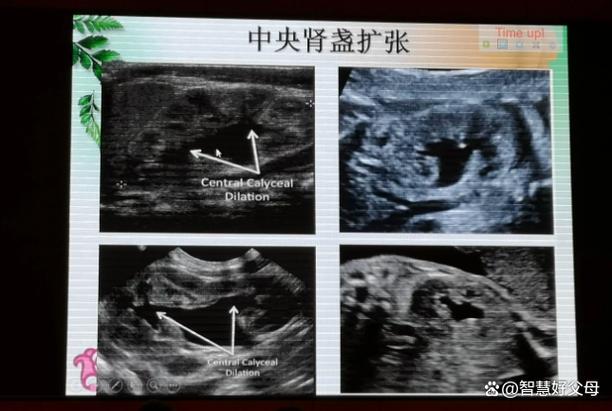

- 肾脏中央的“无回声区”增大:在B超图像上,正常的肾盂是一个小的、无回声的(黑色的)区域,当它扩张时,这个黑色的区域会明显变大。

- 测量数据:B超报告上会给出一个关键的数值——肾盂前后径,这是判断严重程度的主要依据。